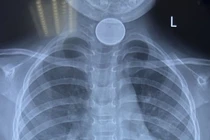

Các bác sĩ Bệnh viện Sản Nhi tỉnh Vĩnh Phúc đã gắp thành công một đồng xu kim loại có hình tròn đường kính 3cm từ trong thực quản cháu bé 4 tuổi ra ngoài.